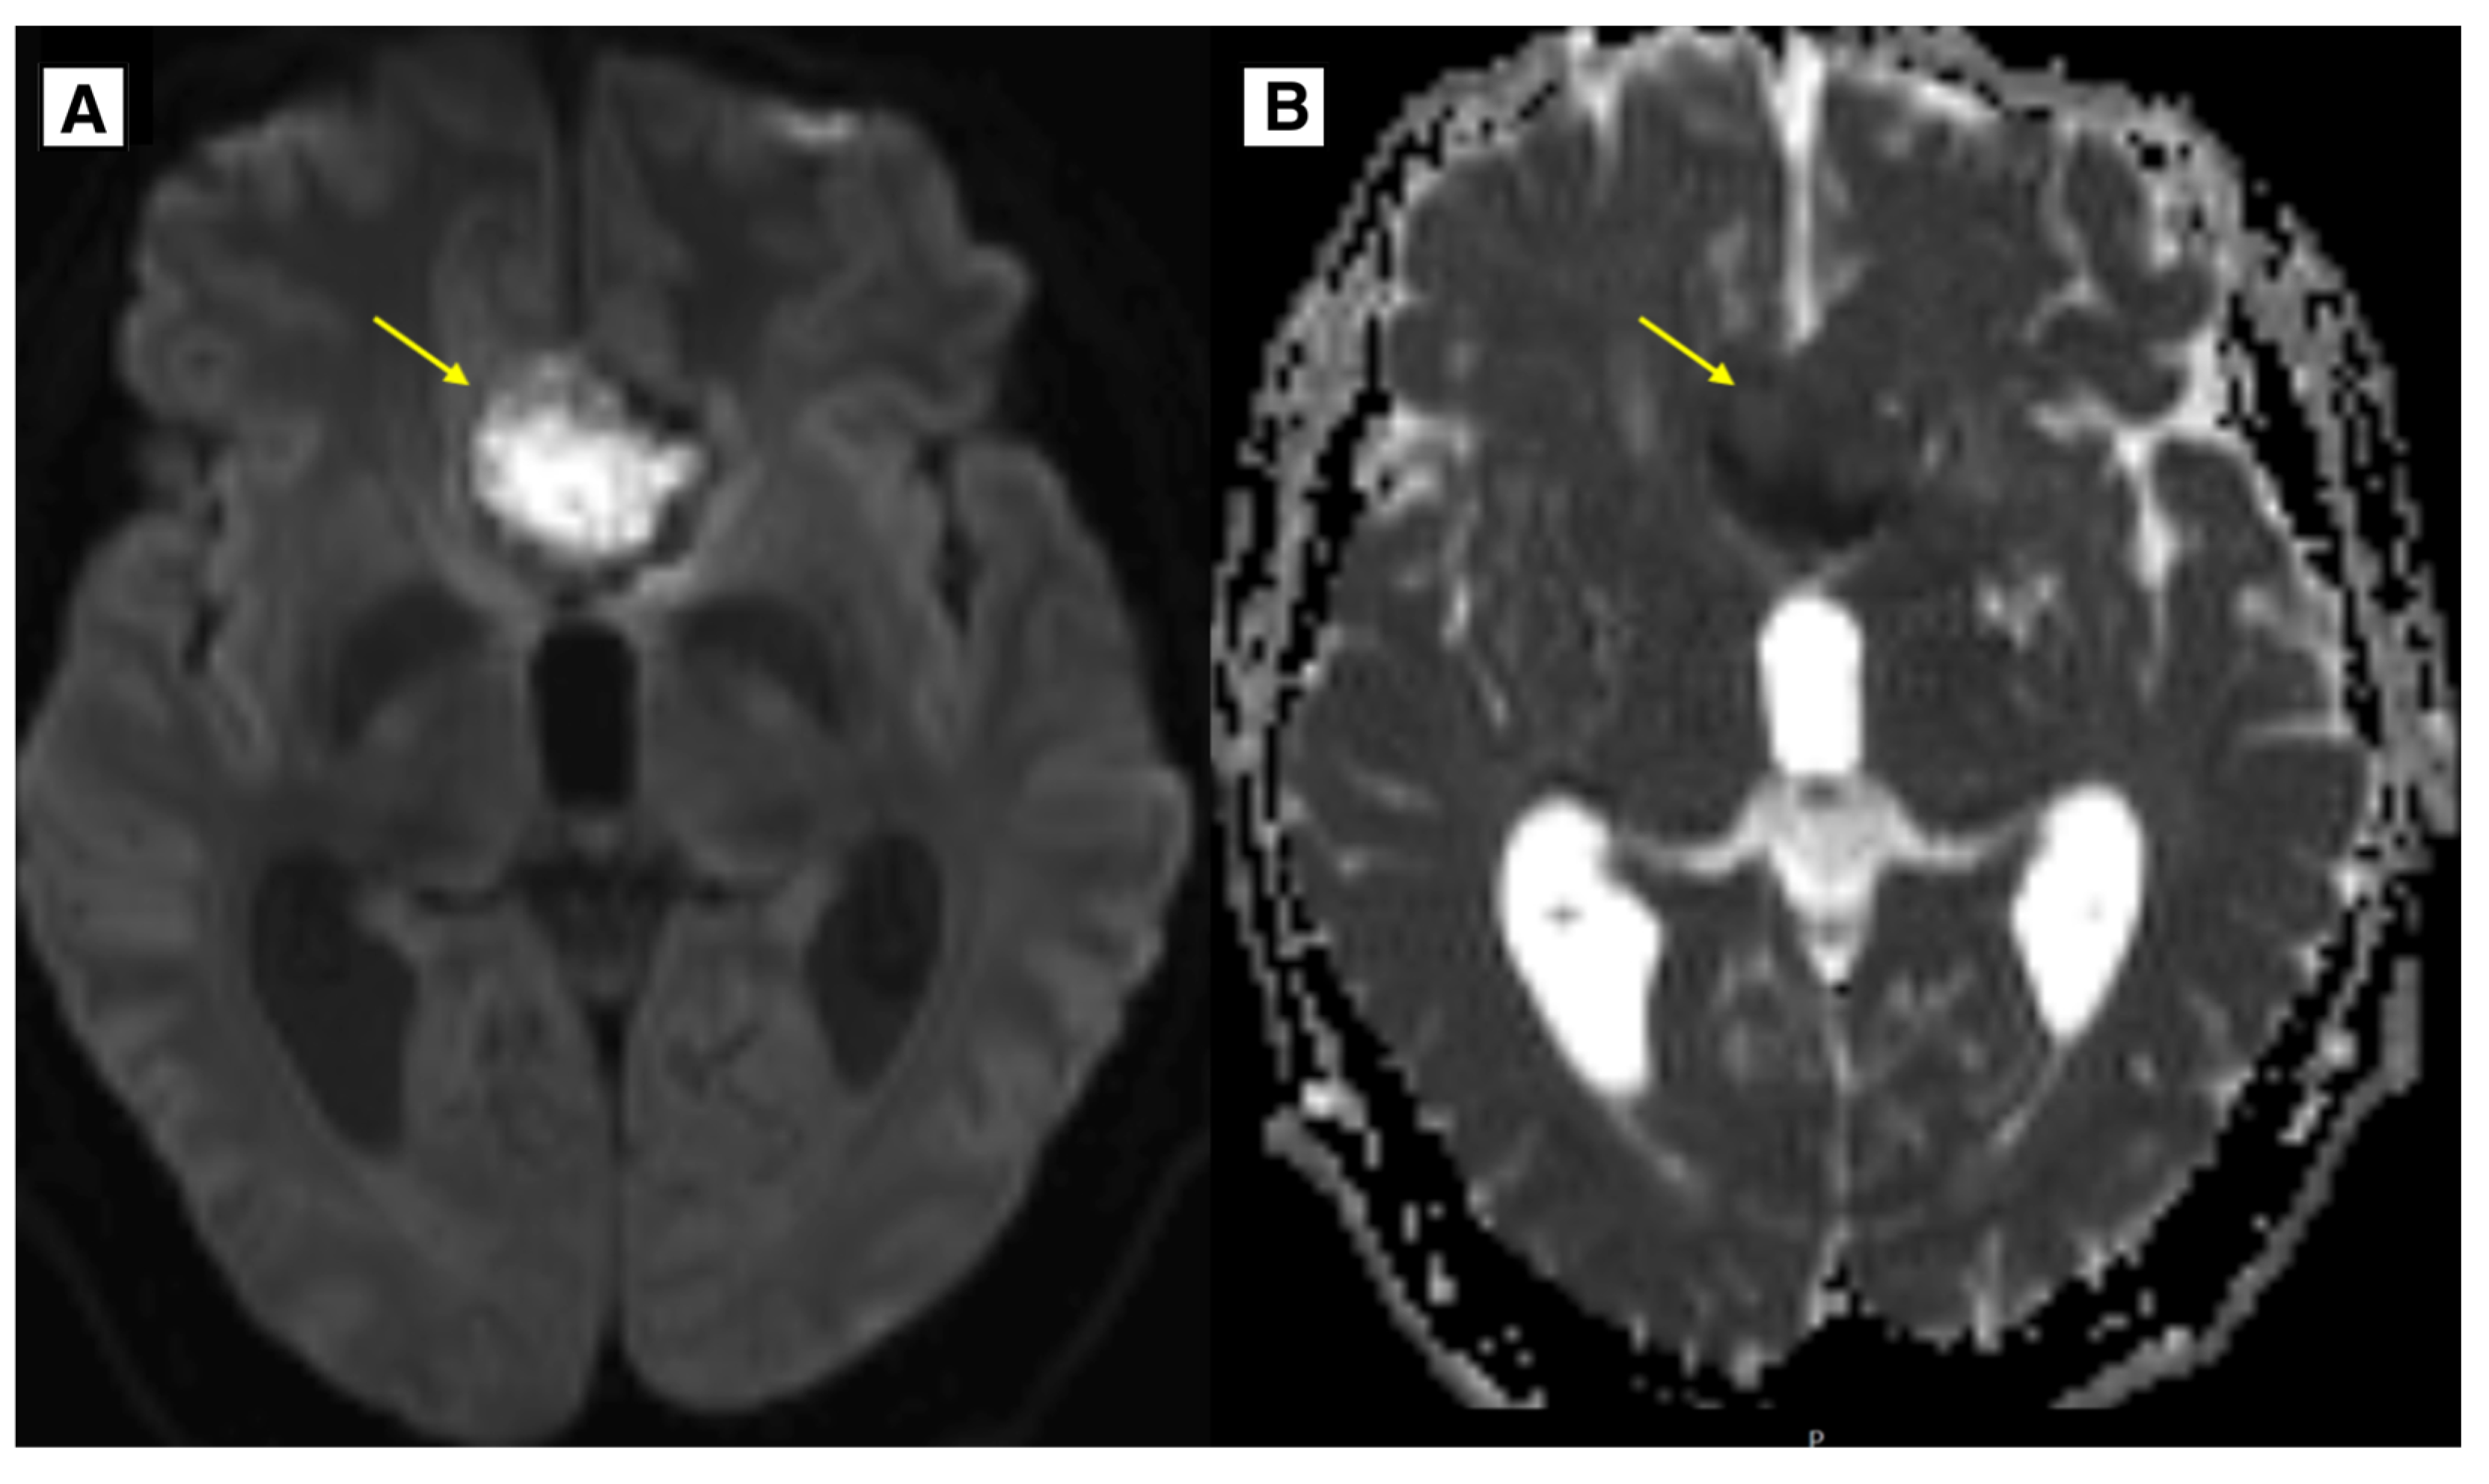

Figure 4.

In the image, A (DWI sequence) and B (ADC map), there is a lesion located in the anterior cranial fossa along the midline, demonstrating slight diffusion restriction and minimally decreased ADC values. Preoperatively, this lesion mimicked an epidermoid cyst; however, histology confirmed it to be a dermoid cyst.

The observed signal characteristics could be explained by the lesion being keratin-rich, which can cause diffusion restriction. Additionally, it is hypothesized that the fatty content of the dermoid cyst was less dense, contributing to the atypical imaging appearance.

The results of the MRI sequences revealed not only typical radiological features of dermoid cysts but also findings that need to be differentiated from other diseases. The hyperintensity on DWI with reduced diffusion mimicked an epidermoid cyst (

Figure 4); T2-FLAIR and T1W sequences showed blood deposits in the brain (

In the available English-language literature, there are only few clinical case reports describing findings typical of epidermoid cysts in brain MRI DWI sequences that have been identified in cases of dermoid cysts. Johnson D.G. et al. present a clinical case where DWI examination revealed reduced diffusion [

21]. A high-intensity DWI signal with reduced diffusion has also been reported in the study by Aksoy F.G. et al. [

34]. Furthermore, the literature includes a reference to a similar finding described by Japanese researchers Shinoyama M. et al. [

35]. In this clinical case, the DWI sequence and ADC map demonstrated slight diffusion restriction and a minimally decreased ADC value. Such radiological findings are characteristic of epidermoid cysts. The epithelial cells of cyst walls secrete the protein keratin, which also contributes to the reduction in the diffusion observed on DWI. Dermoid cysts also contain keratin, and if the fat content within the cyst is low, it can mimic the radiologic features characteristic of epidermoid cysts. This can potentially lead to diagnostic errors in the preoperative period. [

34,

36]. Since these findings are rarely discussed, they represent some of the novel contributions of this article.

The keratin-rich nature of the lesion, which can result in diffusion restriction, may account for the observed signal characteristics. Furthermore, the unusual imaging appearance is thought to have been caused by the dermoid cyst's less dense fatty content (